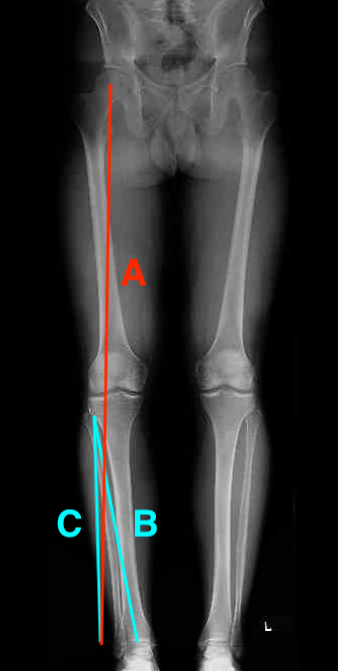

B. Miniaci method

Line A: Desired mechanical axis

- center of the hip to new desired weight bearing axis on lateral tibial plateau

- Fujisawa point (62% from the edge of the medial tibial plateau)

- slightly lateral to the lateral tibial spine

- extend this line to the level of the ankle

Line B: Center of ankle to pivot point on the proximal lateral tibia

Line C: Lateral pivot point to meet Line A

The angle between B and C is the angle of the desired correction